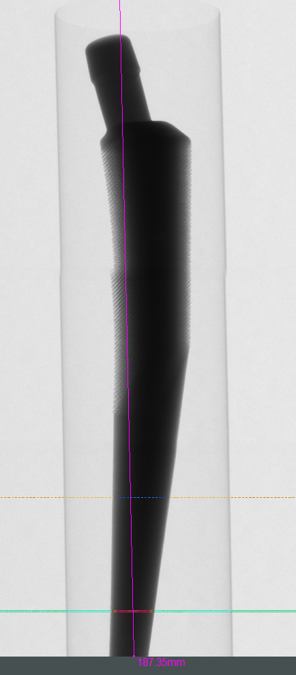

显微 CT 技术在骨修复和再生研究中有着重要作用。通过对植入物和修复材料进行三维成像,可以评估其在骨组织中的整合和效果。

使用 NEOSCAN 台式显微 CT 以 20 微米尺寸扫描钛合金髋关节植入物,植入物长达 18.7 cm。可获得无伪影的高质量图像,清晰展示其内部结构和尺寸大小。